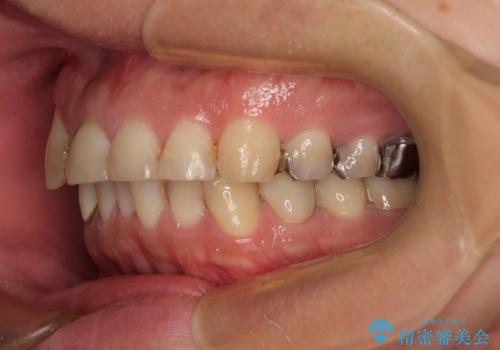

他の銀歯も気になっており、セラミックにしたいとの要望があり、詳しくお話をすると、デコボコの歯ならびも整えたいとのことでした。

矯正治療にやや時間がかかりましたが、歯列はきれいに整い、気になっていたむし歯や銀歯は自然な色合いに仕上がりました。